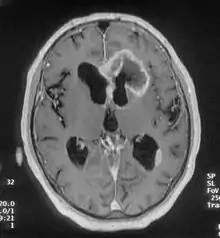

There are many different causes of frontal lobe epilepsy ranging from genetics to head trauma that result in lesions in the frontal lobes. Although frontal lobe epilepsy is often misdiagnosed, tests such as prolonged EEG monitoring and/or a MRI scan of the frontal lobes can be administered in order to reveal the presence of a tumor or vascular malformation. Unlike most epileptic EEGs, the abnormalities in FLE EEGs precede the physical onset of the seizure and aid in localization of the seizure's origin.[3] Medications such as anti-epileptic drugs can typically control the onset of seizures, however, if medications are ineffective the patient may undergo surgery to have focal areas of the frontal lobe removed.